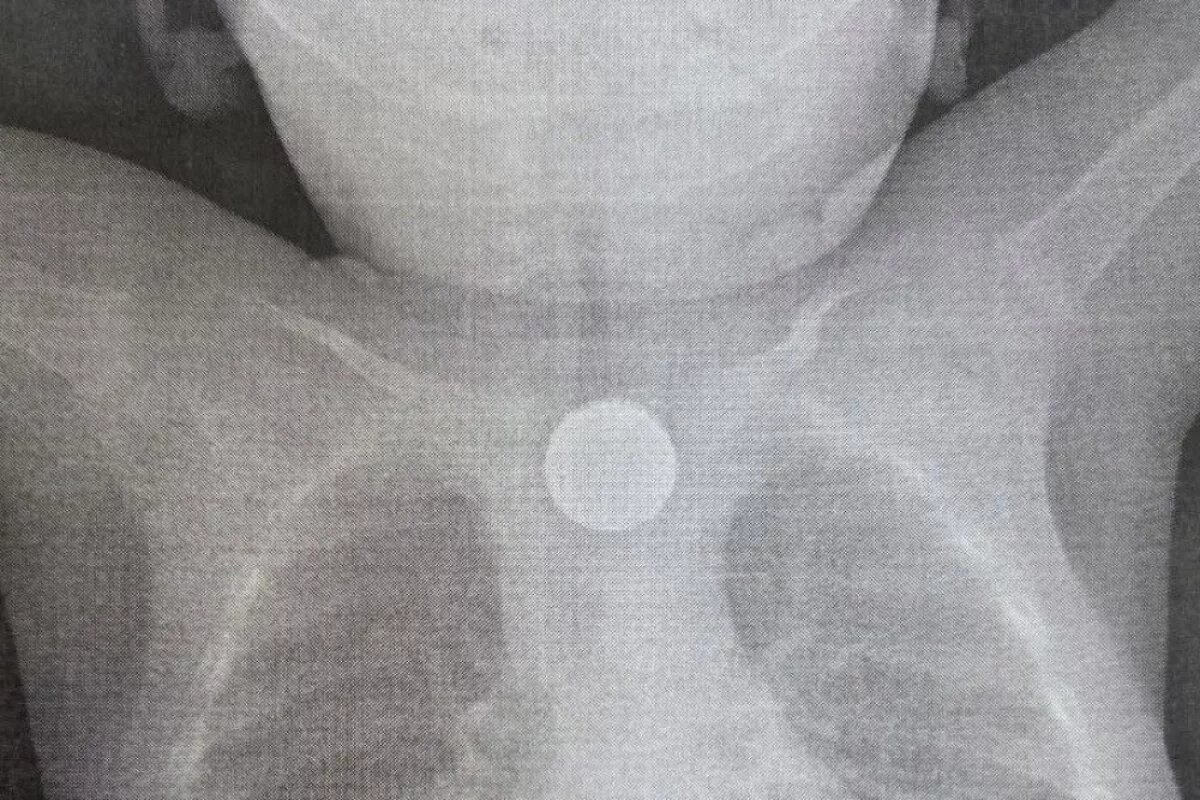

В приёмно-диагностическое отделение больницы доставили годовалого малыша с тревожными симптомами: многократная рвота, повышение температуры, появление хрипов при дыхании. Бригада врачей с помощью эндоскопии вытащила из пищевода ребёнка двухрублёвую монету и дисковую литиевую батарейку.

«Находившаяся в пищеводе батарейка вызвала химический ожог третьей степени, который представлял серьёзную угрозу для жизни ребёнка, — рассказали в медучреждении. — В настоящее время состояние маленького пациента стабилизировалось. Он находится в отделении анестезиологии и реанимации под круглосуточным наблюдением. После дальнейшей стабилизации его переведут в профильное отделение».